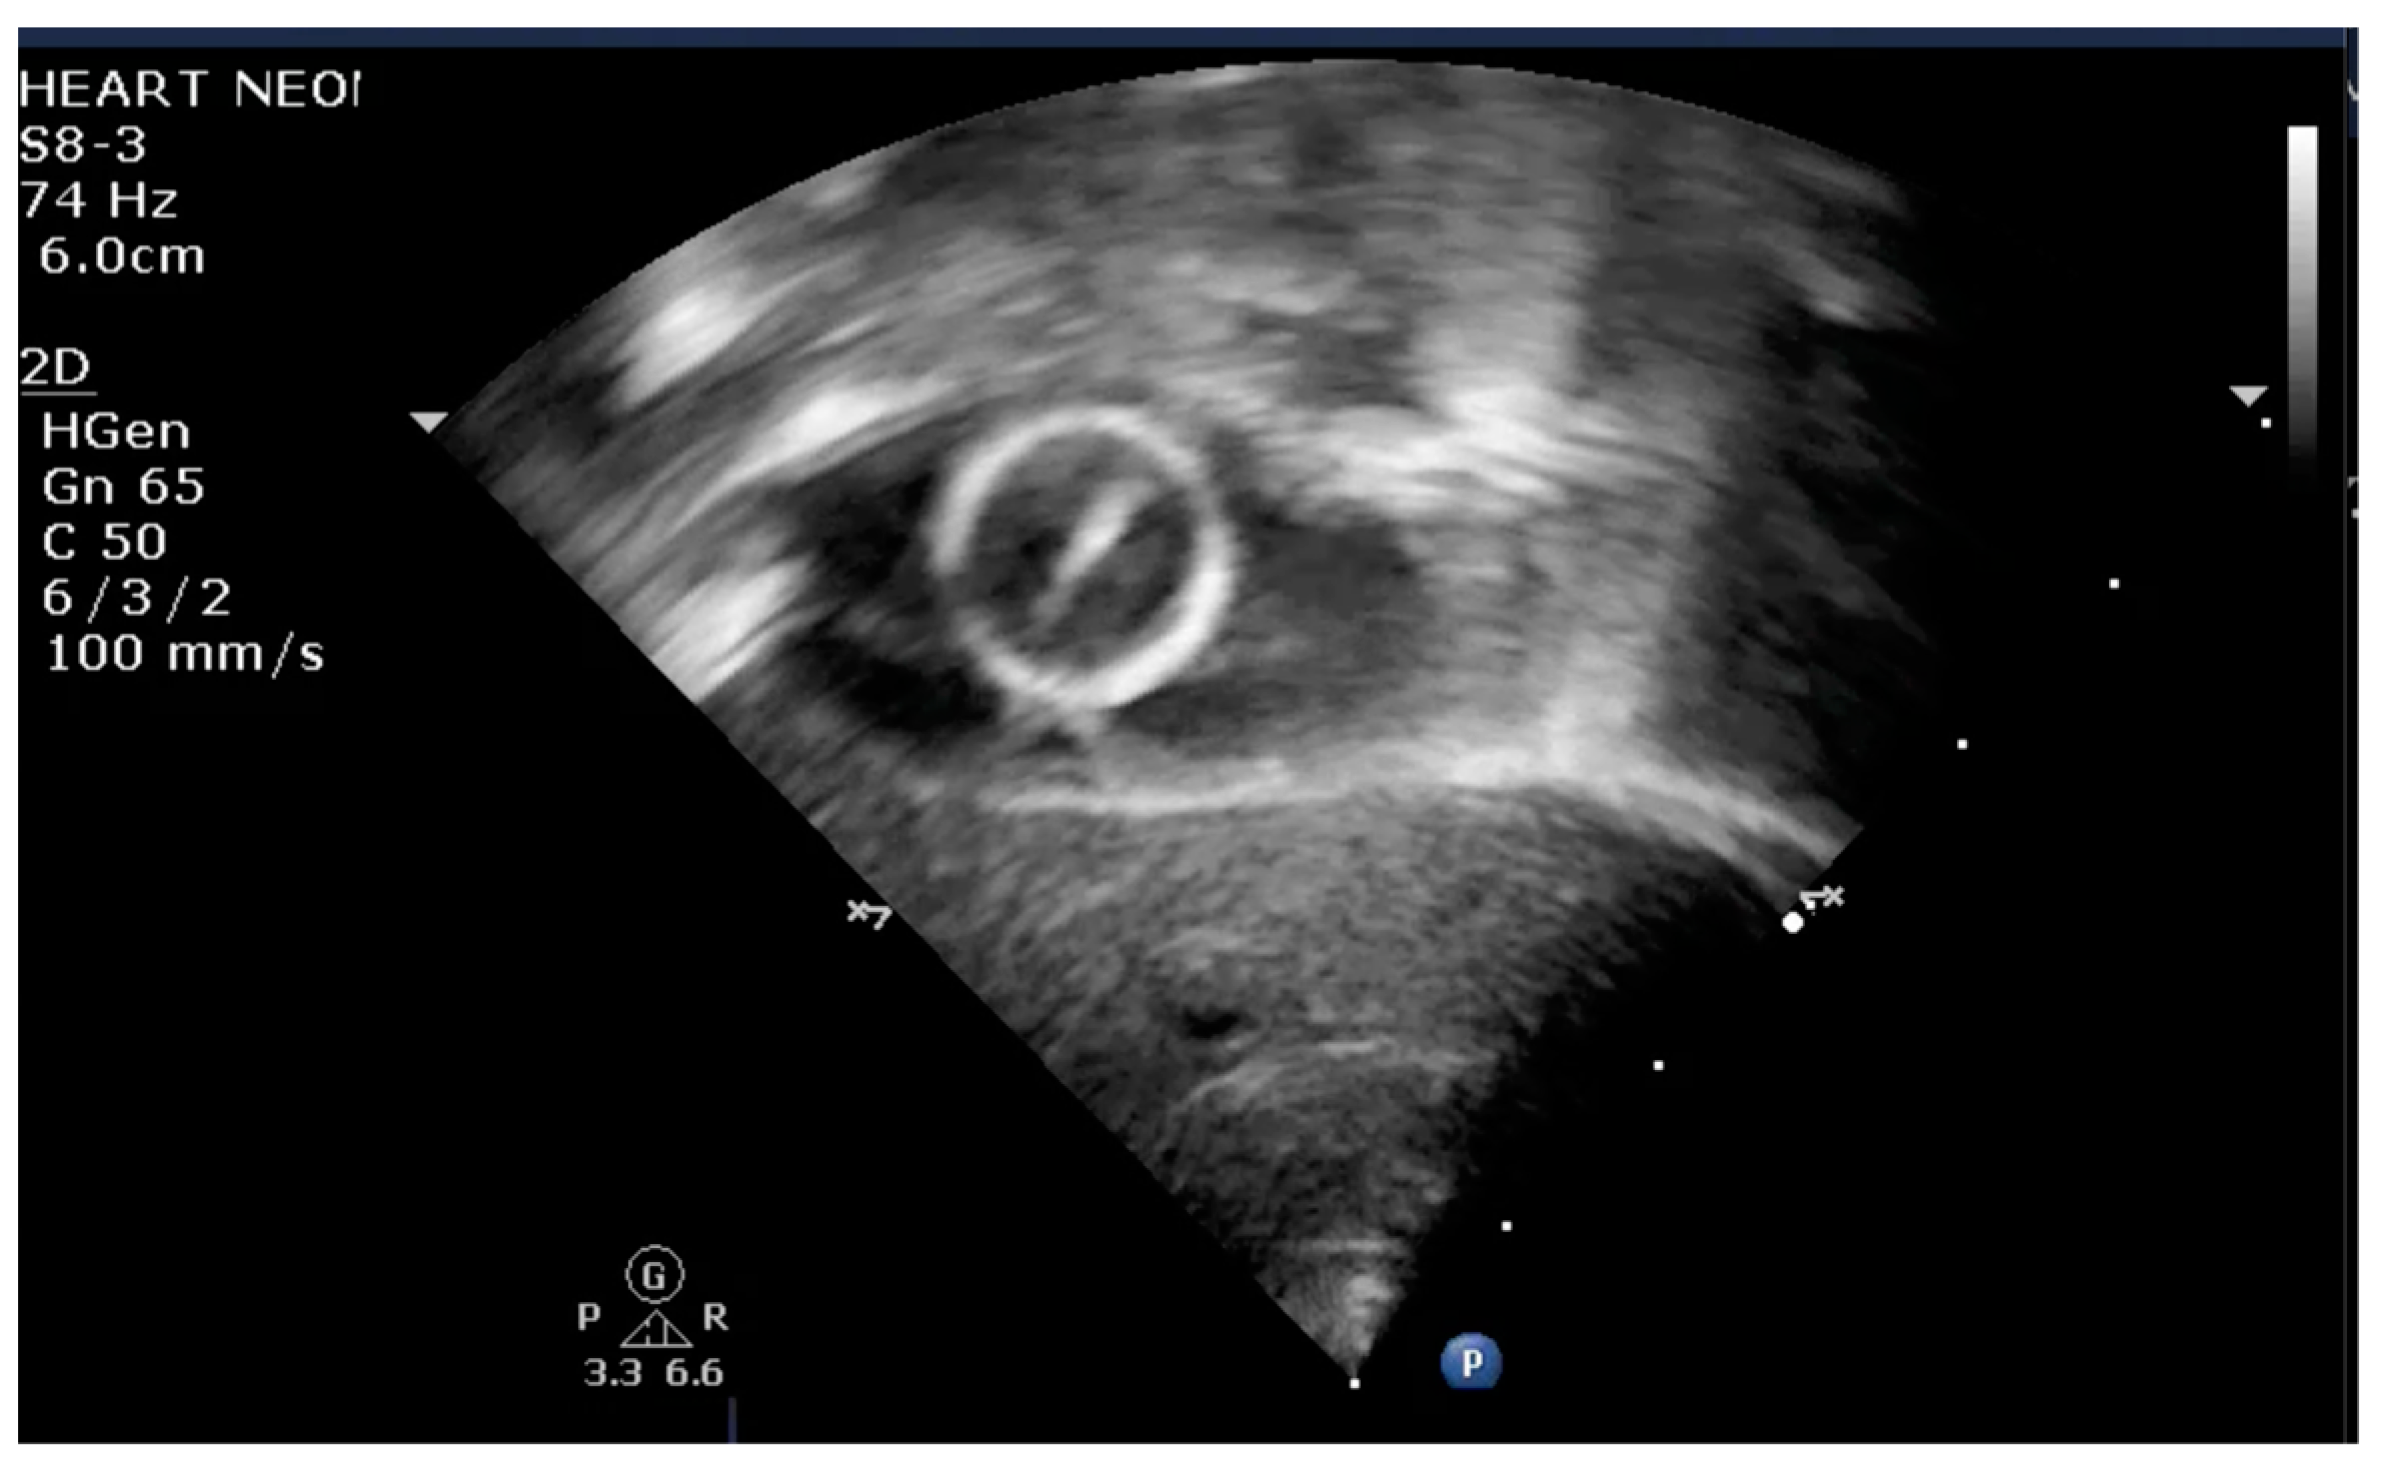

The indication for balloon atrial septostomy was made based on clinical status (low systemic arterial oxygen saturation) correlated with tissue hypoxia (persistently elevated lactate level), echocardiographic assessment (patency and size of interatrial septal defect, ductus arteriosus, and interventricular septal defect), and anticipated delay to surgery. The procedure was performed according to the institutional protocol, at the patient’s bedside, under general anesthesia, and using the Rashkind pull-back technique under echocardiographic guidance (Figure 1 and Figure 2). Vascular access was obtained via a sterile technique via the femoral or umbilical vein. The procedure was repeated several times until satisfactory atrial communication was obtained. The success of BAS was clinically objectified by increasing systemic arterial saturation by at least 10% and echocardiographically objectified by increasing interatrial communication (Figure 3).

Figure 3.

Transthoracic echocardiography subcostal view: large communication at the level of IAS after BAS.